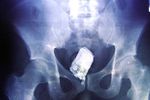

Jakarta - Sinar X adalah teknologi mutakhir yang memudahkan para dokter untuk melihat isi tubuh manusia tanpa harus membedahnya. Bukan hanya organ yang kelihatan, kadang-kadang para dokter juga menemukan perkakas seperti kunci mobil, ponsel hingga botol minum yang terjebak di dalam tubuh pasien. (Foto: Pool)